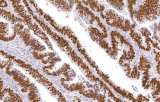

Los anticuerpos validados CE/IVD diseñados para flujos de trabajo diagnósticos de IHQ se utilizan ampliamente para apoyar protocolos de tinción estandarizados y reproducibles en laboratorios clínicos. Estos reactivos son particularmente relevantes para laboratorios de patología que operan en entornos diagnósticos regulados donde se requiere fiabilidad analítica y cumplimiento normativo. Desde una perspectiva científica, la IHQ funciona como complemento a la histomorfología al resaltar proteínas específicas de linaje, marcadores de diferenciación celular y antígenos tumorales asociados que definen las neoplasias genitourinarias.

Estandarización para laboratorios clínicos

Los anticuerpos CE/IVD apoyan flujos de trabajo de tinción e interpretación estandarizados, alineándose con prácticas diagnósticas guiadas por guías descritas en revisiones de patología genitourinaria.